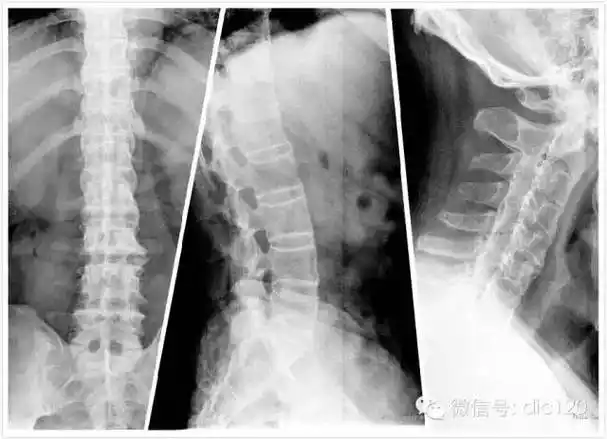

强直性脊柱炎典型影像表现及其病理生理-medsci.cn